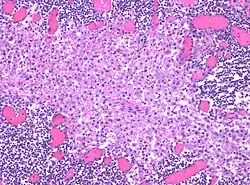

In medicine, histiocytosis is an excessive number of histiocytes[1] (tissue macrophages), and the term is also often used to refer to a group of rare diseases which share this sign as a characteristic. Occasionally and confusingly, the term histiocytosis is sometimes used to refer to individual diseases.